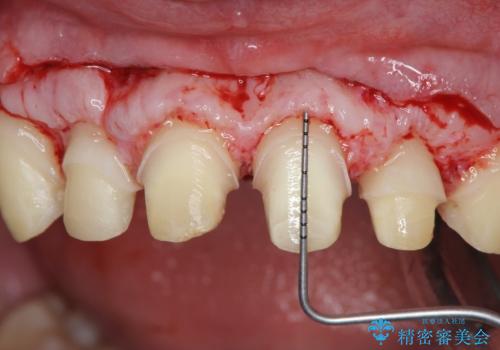

ただ、白いオールセラミッククラウンを製作・装着するのではなく、将来にわたり安定した状況を獲得するため、歯周外科を行い歯ぐきと周囲の歯槽骨の形態を整えていきます。

歯周外科を行ったことで、歯ぐきの形態や腫れが改善され、審美性だけでなく清掃性も大きく改善することができました。